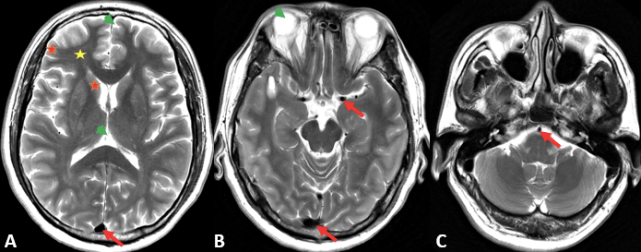

图片

图 1. T2WI 上脑白质呈稍低信号(黄色星);脑灰质(皮层和灰质核团)呈稍高信号(红色星);脑脊液及玻璃体呈明显高信号(绿色箭头);颅内大血管(静脉窦、大脑中动脉及基底动脉)流空信号,呈低信号(红色箭)